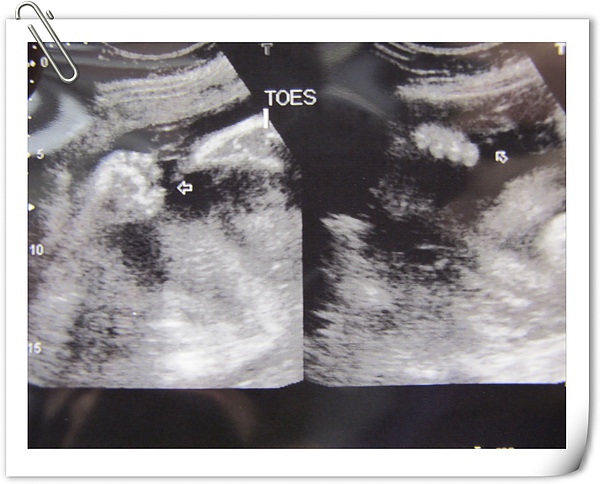

二隻小腳抬的很高,有正常的五根指頭